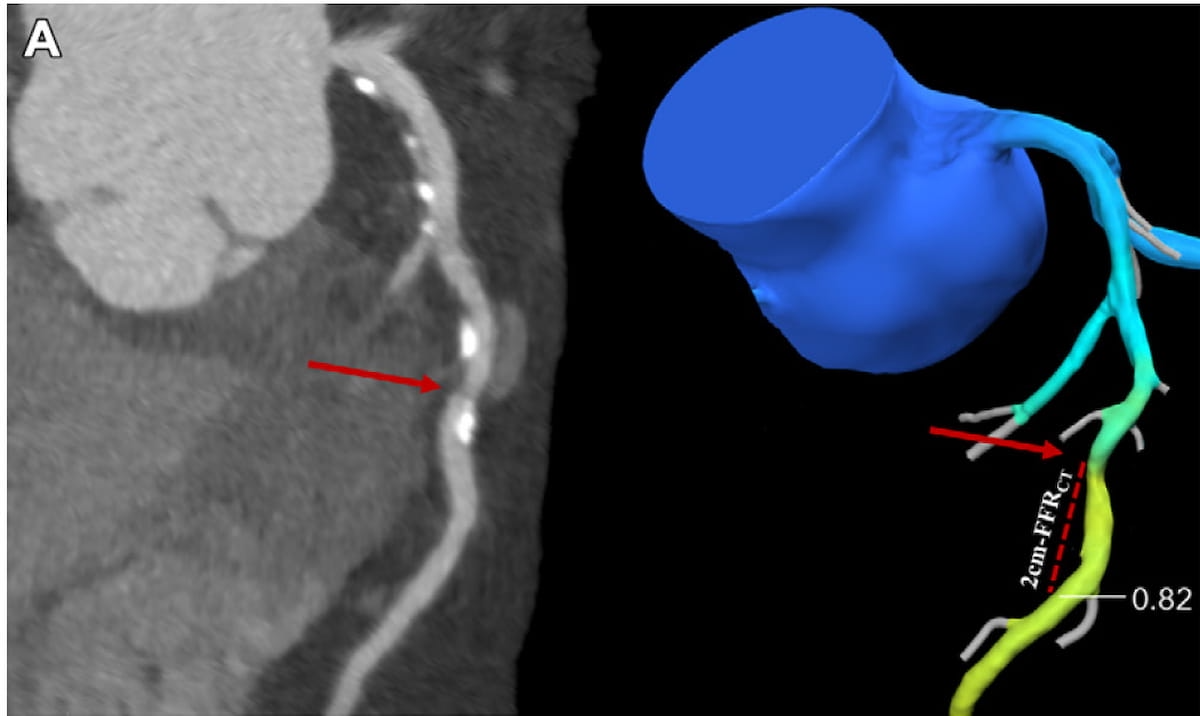

Here one can coronary computed tomography angiography (CCTA) imaging (left) and CCTA-derived fraction flow reserve (FFR) (right). In a recent study of people with stable angina and coronary stenosis, researchers found that normal CCTA-FFR values (greater than 80 percent) were associated with significantly lower risks of all-cause death and spontaneous myocardial infarction (MI) than those with abnormal CCTA-FRR values (>80 percent). (Images courtesy of Radiology.)

For the prospective study, recently published in Radiology, researchers assessed the impact of CCTA-FFR findings on three-year outcomes for 900 patients with stable angina and coronary stenosis. The study authors noted that 523 study participants had normal CCTA-FFR results, and 377 participants had abnormal findings on CCTA-FFR, according to the study. The study authors defined an abnormal CCTA-FFR value as less than or equal to 80 percent.

The researchers found that study participants with abnormal CCTA-FFR findings had a 3.2-fold higher risk of all-cause death and spontaneous MI, and an 8.8-fold higher risk of cardiovascular death and spontaneous MI in comparison to those with normal CCTA-FFR findings.